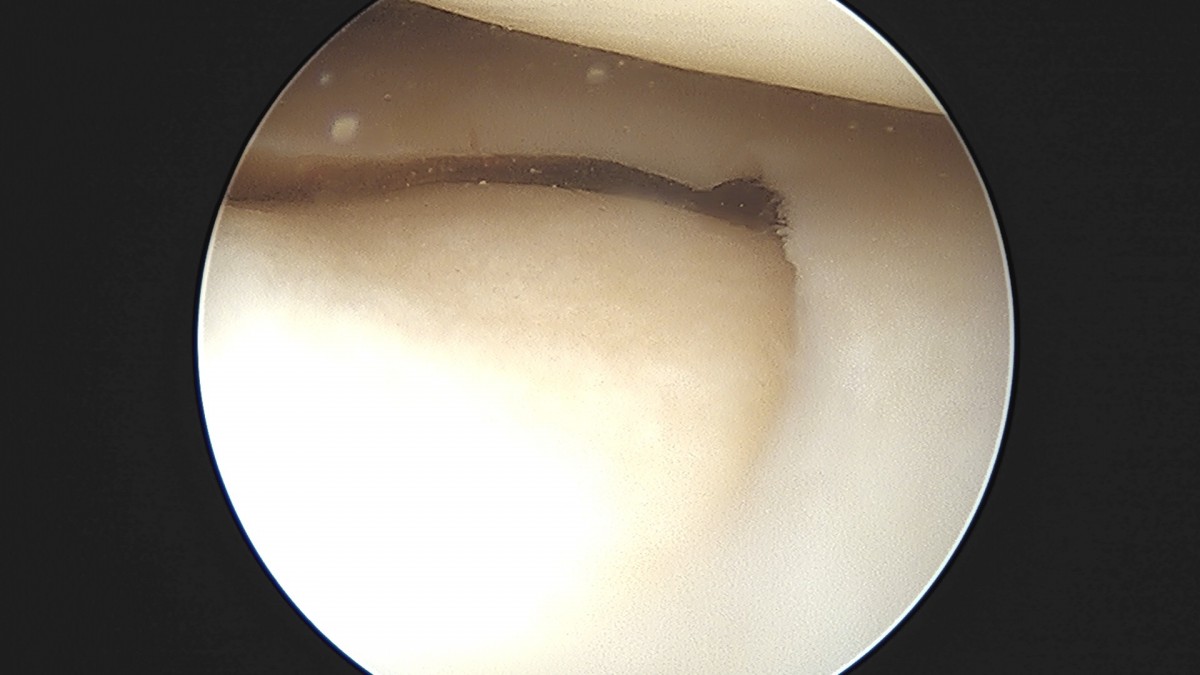

이재상원장님 무릎 반월상 연골판 절제술 조미O 환자

작성자 최고관리자 댓글 0건 조회 368회 작성일 25-09-16 16:01